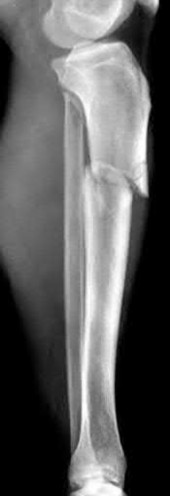

Question 19:

A 28-year-old male sustains a closed comminuted tibial shaft fracture. Two hours post-injury, he develops severe leg pain unyielding to narcotics. His blood pressure is 120/80 mmHg. Intracompartmental pressure monitoring is performed. Based on current guidelines, which measurement dictates an emergent 4-compartment fasciotomy?

Correct Answer: Delta pressure (Diastolic BP - Compartment Pressure) < 30 mmHg

Explanation:

Acute compartment syndrome is classically defined by tissue hypoperfusion. The absolute compartment pressure is less reliable than the differential pressure (Delta P). A Delta P (Diastolic Blood Pressure minus Compartment Pressure) of less than 30 mmHg is an absolute indication for emergency fasciotomy, as capillary perfusion gradient is lost when tissue pressure approaches the diastolic pressure.